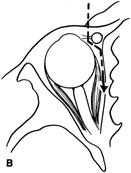

Lateral orbitotomy provides excellent access to deep lesions in the subperiosteal, peripheral, or intraconal space lateral to the optic nerve (Fig. 8A, B).

Fig. 8. Coronal (A) and axial (B) views in an illustration of areas (shaded) amenable to lateral orbitotomy.